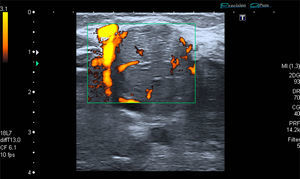

The patient was a 53-year-old man with no significant medical history. He presented with a painless mass in anterior forearm, reporting no previous injury. Physical examination confirmed the presence of a hard, immobile mass measuring less than 1cm. He came to the rheumatologic examination room, where he underwent soft tissue ultrasound (Toshiba Aplio®300). A round mass measuring less than 1cm was observed. It was iso/hypoechoic on gray scale images, was moderately well-defined, and was joined to a vessel that fed it (Fig. 1). On color Doppler, there was high echo intensity throughout the entire lesion, more intense on the periphery (Figs. 2 and 3). As there were findings that raised suspicion, such as heterogeneity, the marked vascularity and the marked Doppler signal (grade 3), magnetic resonance imaging was performed. This study revealed a round, well-defined form measuring 1cm, with hyperintensity on T1-weighted images, which pointed to a metastatic lesion (Fig. 4).